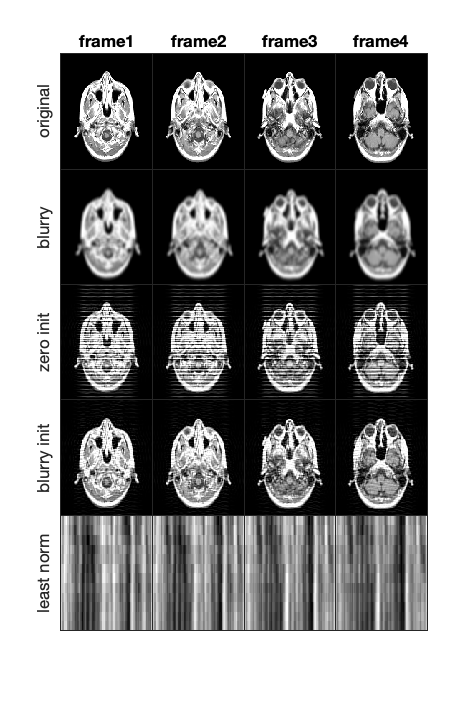

4.2. Video Deblurring

We address the problem of recovering a true video tensor from a blurry video tensor , given a known blurring operator. Specifically, we assume that each frame of the video undergoes blurring via a circular convolution kernel . Without loss of generality, the kernel can be extended to by padding it with zeros. Then, the relationship between the slices of the blurry and true video tensors can be expressed as the matrix system

where is a circulant matrix and denotes row of , and the matrices and are obtained by the illustrated matricization of and , i.e., by defining the columns by the vectors obtained by vectorizing frontal slices of and . Using the definition of the t-product 1, we can rewrite this system as the t-linear system

where the -th frontal face of the blurring tensor is given by and and are obtained by suitably refolding and respectively to dimensions .

In our experiment, we consider the recovery of 12 frames of twice blurred MRI images of size . First, we circularly blur the images using a Gaussian filter followed by a averaging filter. These operations amount to solving a t-product system, , where represents the original images, the blurred images, and and represents the tensor obtained by the successive Gaussian blurring and average blurring operators.

We can visualize the results of our experiment in Figure 13, which shows that we can recover the frames with a residual error of about for TRBAGS, while the error for TRBGS is larger. Interestingly, TRBAGS performs better than TRBGS, with fewer artifacts in the recovered images. We believe that the pseudoinverse computation may be the source of the larger numerical errors in TRGBS. Although the error is non-negligible, the recovered images qualitatively match the original video data much more closely than the blurred versions, especially for TRBAGS, demonstrating the experiment’s effectiveness for practical purposes. We omit factorized versions since the results in Section 4.1.3 show that they have performances comparable to TRBGS and TRBAGS, and thus, we would expect the same qualitative results.